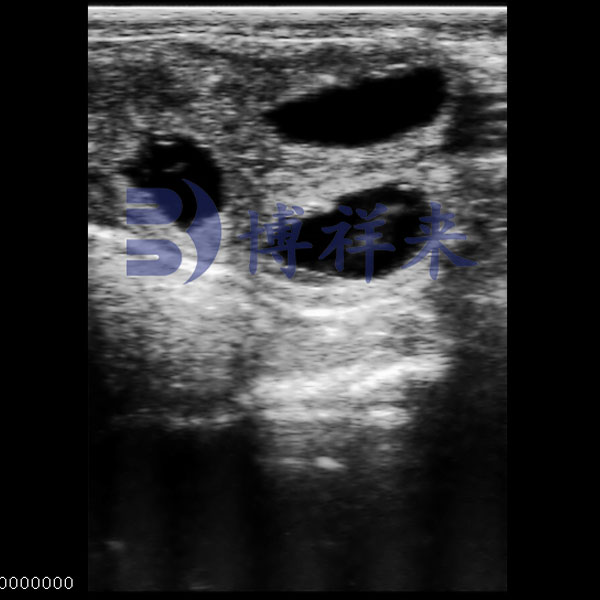

Bovine Uterus Ultrasound

● Shows complete uterine section with clear internal zoning.

● Balanced contrast for identifying tissue makeup.

● Displays wall thickness and lumen features.

● Suitable for reproductive assessment.